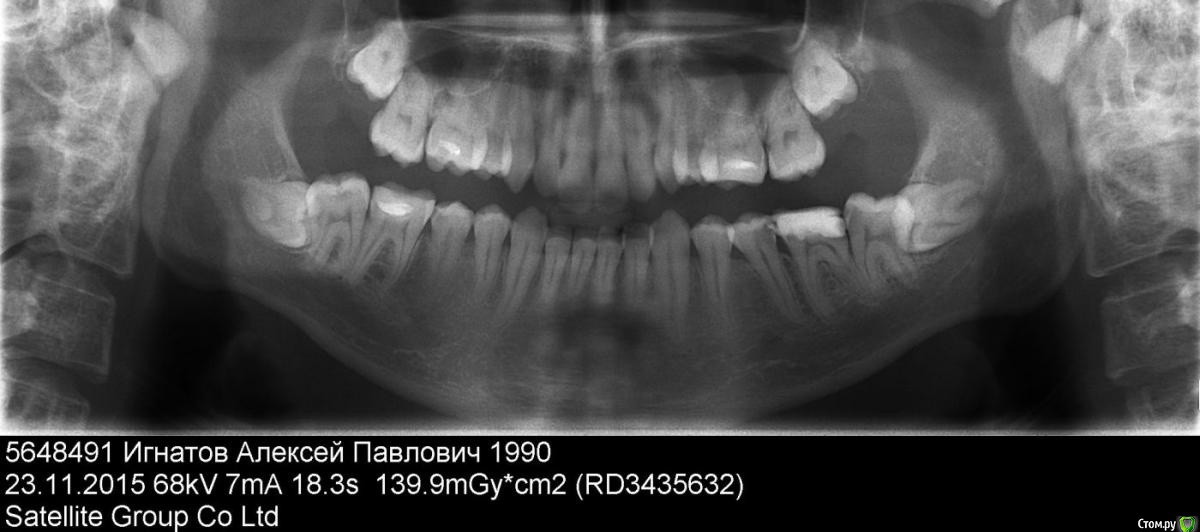

LexIgnatov Опубликовано 2 декабря, 2015 Поделиться Опубликовано 2 декабря, 2015 Здравствуйте, лечу сейчас 6 зуб слева, удалили нервы. Следующий на очереди 5ый с кариесом, тоже под удаление нервов. В клинике пока не определились что делать с 7 и 8 слева.7ой наполовину прикрыт десной. На открытой части кариес. Если потребуется удалять нервы будет проблемно - рот плохо открывается. Рассматривают вариант удалить 7-ку и через её полость удалить 8ку, но это целая операция. У матери в 50 лет 8 не прорезались и не беспокоят. Посоветуйте что делать.Сегодня вот от лечения 6-ки покалывания иррадиируют в верхнюю челюсть. Уже думаю не сделать ли КТ или МРТ, может нерв задели. Ссылка на комментарий

LexIgnatov Опубликовано 7 декабря, 2015 Автор Поделиться Опубликовано 7 декабря, 2015 (изменено) Здравствуйте, был у ортодонта - посоветовали удалить 8-ки снизу, чтобы затем выровнять зубной ряд (первые зубы в нижнем ряду слегка повёрнуты вокруг вертикальной оси, наползая друг на друга). Затем был у хирурга - совет совершенно другой. Удалить 7ки. Обосновывает тем что 8-ки сидят глубоко в кости и удалять их проблема. А левая 7-ка уже в состоянии хорошего кариеса под удаление нервов. Вариант с удалением гиблых 7-к нравится больше, чем распил челюсти для извлечения 8-к, но насколько часто такое применяется? Что будет после с 8-ками? Так и останутся лежать в челюсти. Мне впринципе для жевания 6 зубов хватает, всё-равно для 7-к внизу нет антагонистов на верхней челюсти. Снимок ОПТГ в первом сообщении. Изменено 7 декабря, 2015 пользователем LexIgnatov Ссылка на комментарий